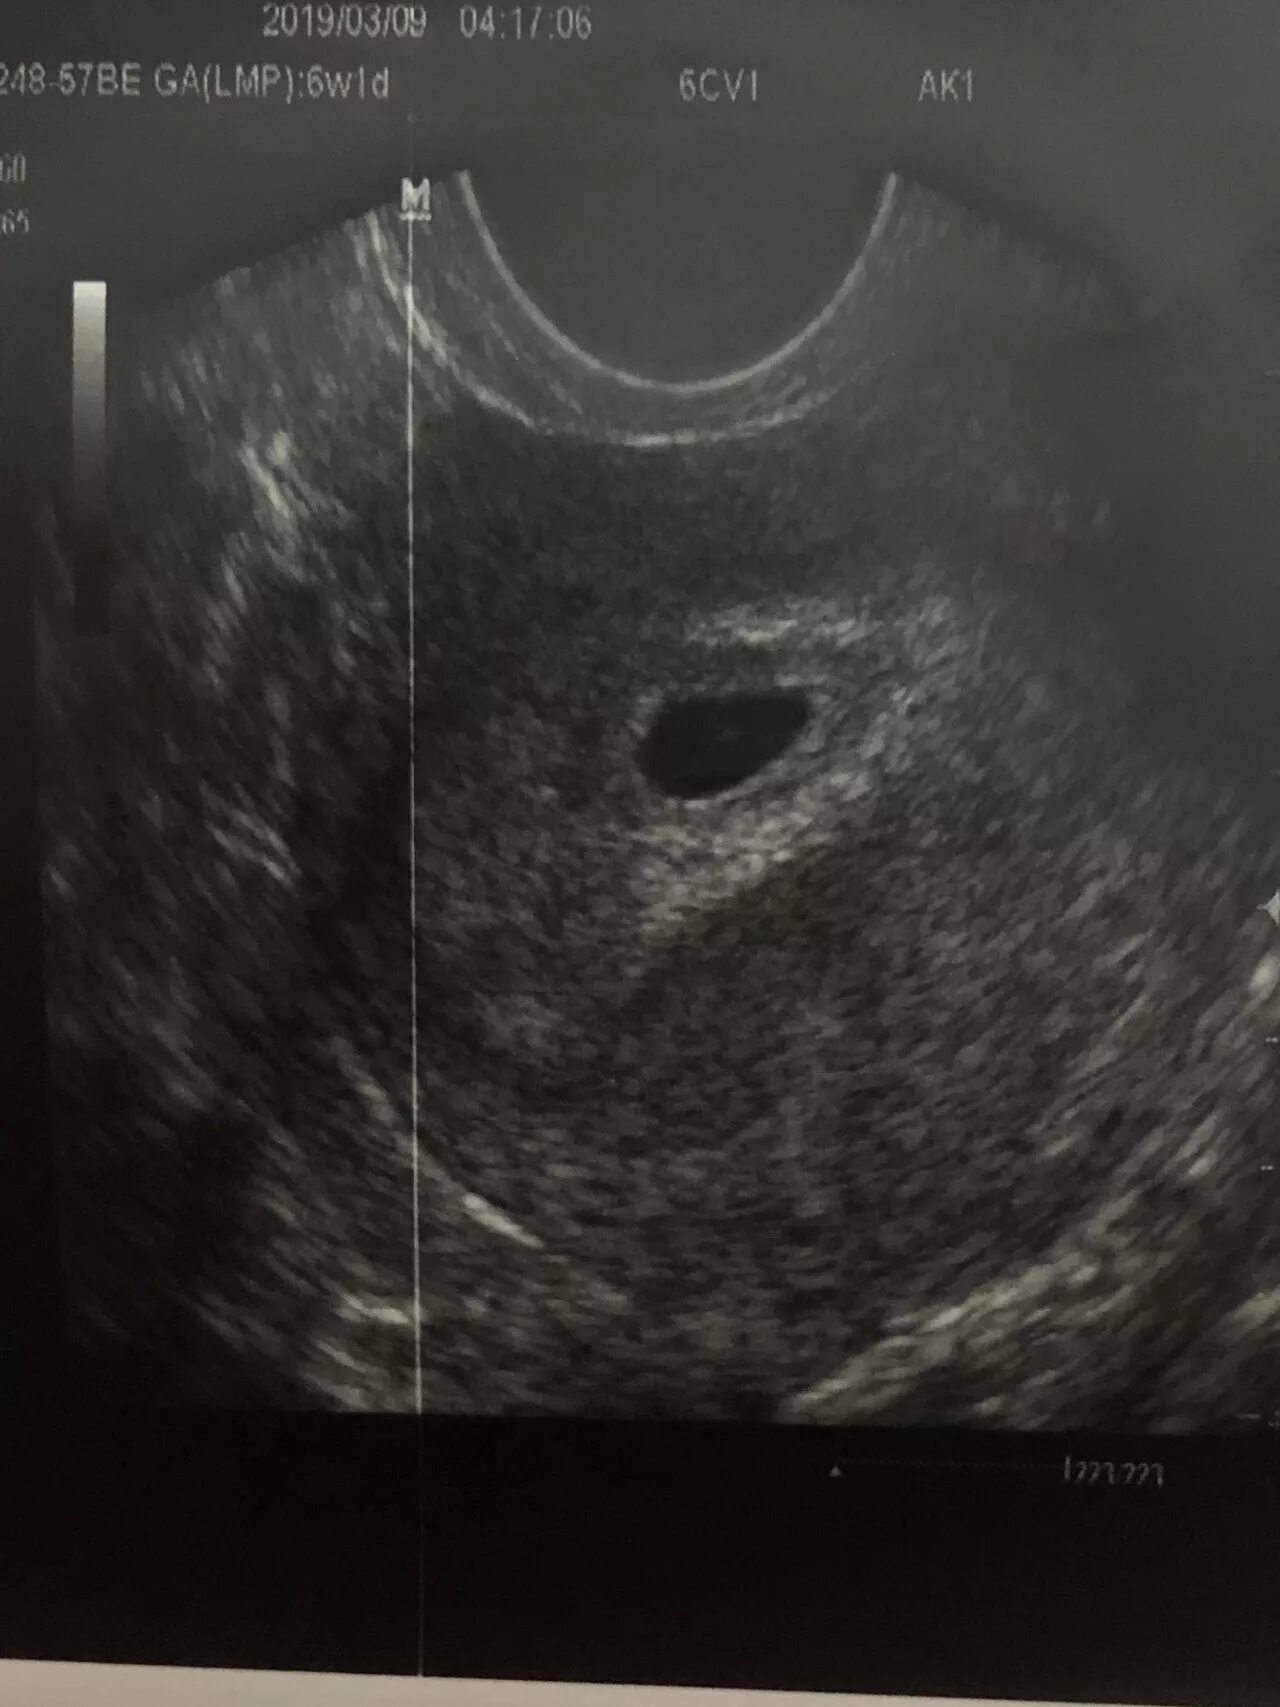

Плодное яйцо 1 5